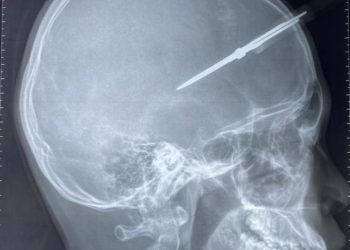

Phẫu thuật thành công cho bé trai bị kéo đâm thủng hộp sọ

Ngày 19/1, Khoa Cấp cứu Bệnh viện đa khoa Đức Giang tiếp nhận trường hợp cháu Phạm Tr H 12 tuổi, trú tại Gia Lâm – Hà Nội bị kéo ...